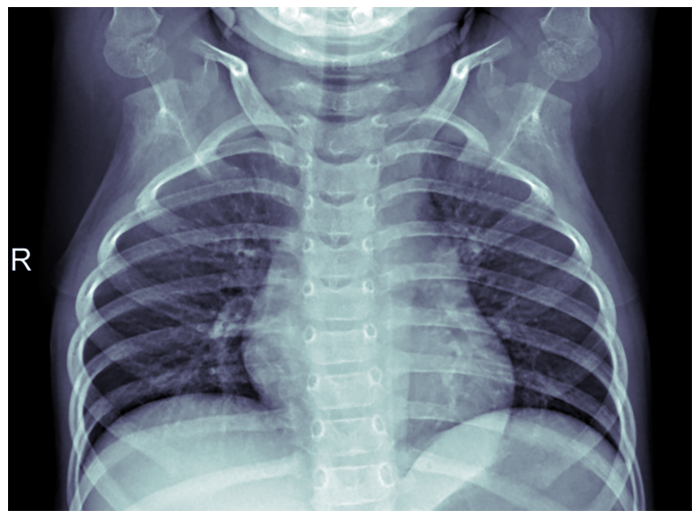

Fig. 4. Radiografie pulmonară - Pneumonie - PAUL MOONEY, 2018 (Chest X-Ray Images (Pneumonia) | Kaggle )

Acesta este locul unde Machine Learning poate fi de ajutor, prin automatizarea procedurii de diagnosticare, care necesită mult timp. În acest exemplu, am folosit librăria TensorFlow împreună cu un model pe TensorHub și setul de date de radiografii toracice de la Kaggle (Fig. 4 este a unui pacient sănătos, iar Fig. 5 este a unui pacient cu pneumonie). Pentru ochiul neexperimentat și chiar pentru cel al unui medic experimentat, acestea ar părea poate greu de distins, ceea ce este de înțeles. Să ne amintim că un medic dedică cea mai mare parte a timpului diagnosticării pacientului și dacă încercăm să distingem cele două scanări putem înțelege de ce.